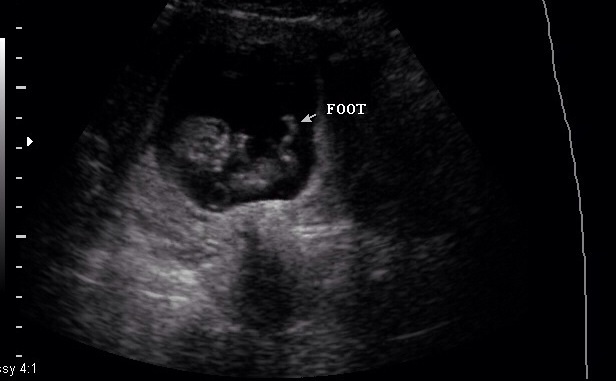

DH and I got a "pregnancy confirmation" ultrasound done at a place here in town (OB okayed it), and we got to see our little bean.

He/she is measuring right on schedule with a strong HB of 176.  Apparently we have a very active baby on our hands, and even the tech was commenting how much the kid was moving around.  I'm in a for a world of fun when I can feel those kicks.